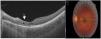

Caso 2: varón, 12 años, origen español. Presentaba cuadro de cefalea y pérdida de agudeza visual (0,8). En fondo de ojo se observaba coriorretinitis focal con vitritis compatible de lesión por toxoplasma y serológicamente mostraba una IgM negativa a toxoplasma, con IgG positiva. Controles posteriores presentaban cuadruplicación de la titulación de IgG. Inició tratamiento antibiótico y corticoides sistémicos. La evolución mostró una cicatización parafoveal con ausencia de fotorreceptores y pequeños quistes en retina, con una agudeza visual normal (fig. 2).

A) Imagen OCT. Se observan espacios quísticos en la capa interna de la retina. Son frecuentes los espacios quísticos en pacientes con toxoplasmosis, se consideran una complicación (quistes llenos de parásitos o signos de inflamación o exudación local). B) Fondo de ojo. Se observa la cicatriz coriorretiniana paramacular nasal coincidente con la imagen de OCT.

Estos 3casos fueron tratados con pirimetamina-sulfadiazina y corticoides orales con buena respuesta clínica. La evolución clínico-serológica ha permitido confirmar el diagnóstico de uveítis por toxoplasma. En la OCT, la retinitis focal con vitritis adyacente es muy característica de la TO. Nuevos signos clínicos hallados en la OCT, tales como la presencia de signos precoces de inflamación (estalagtitas) (fig. 1), o residuales, como quistes en la retina5 (fig. 2) no son específicos de la toxoplasmosis y se han descrito en el contexto de otras enfermedades (linfoma intraocular). No obstante, nos pueden ayudar para sospecha diagnóstica de la enfermedad y evitar técnicas más cruentas como la determinación de PCR en vítreo. La presencia de los quistes residuales, además, podría estar relacionada con la patogénesis de las reactivaciones. La sistematización del uso de la OCT y futuros estudios podrían colaborar para la comprensión de la enfermedad.